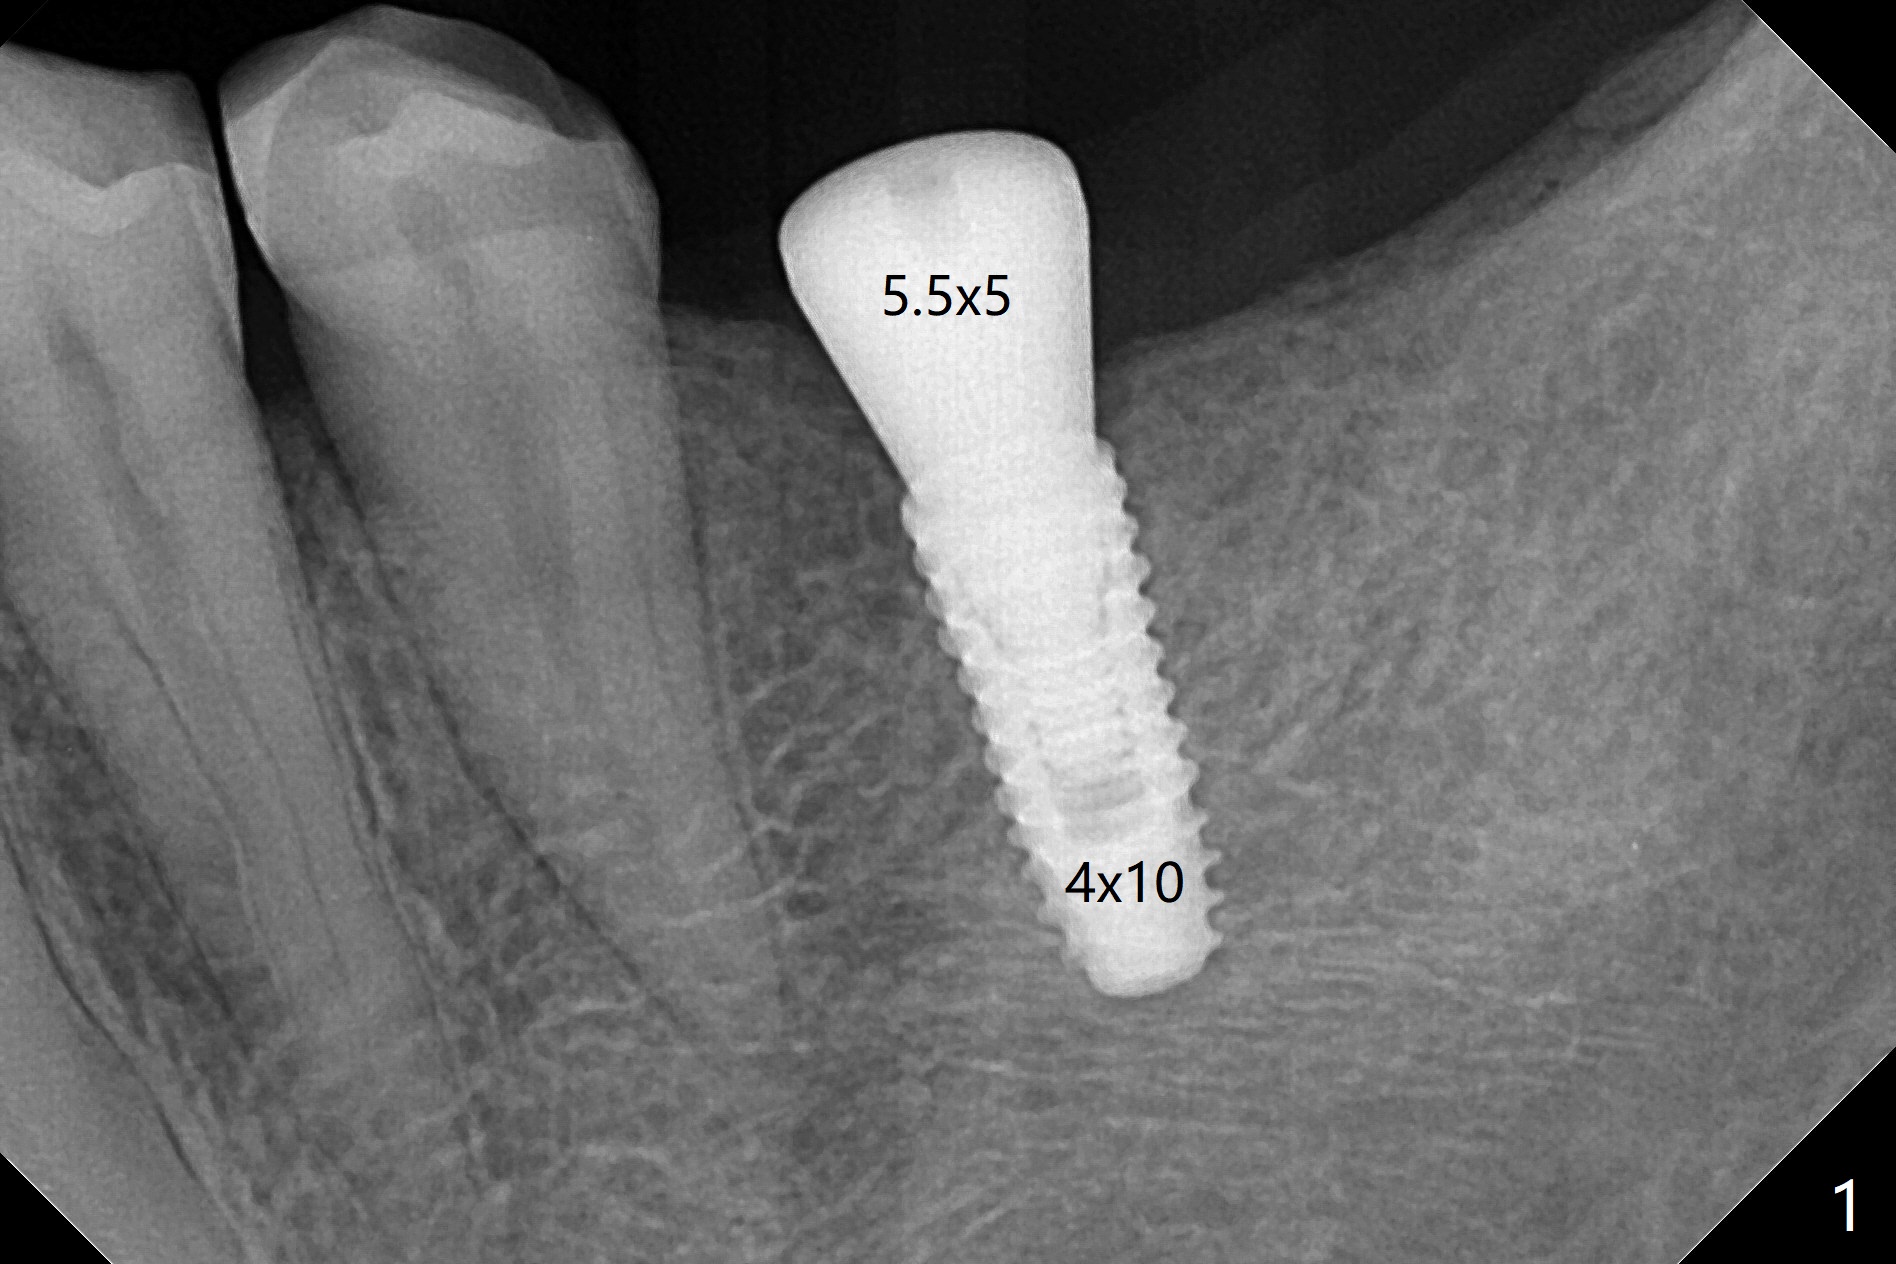

术前即刻发现19号牙位牙槽嵴角化龈不宽,所以选择切开,另一个好处是植体植入后可以清楚观察到植体(5-10 Ncm)刚刚好位于舌侧牙槽嵴下,而且后者最薄,与设计一致。使用6毫米Profile Drill后,观察斜坡也容易,最后放置5.5x5毫米愈合基台(图一:好像没有就位)。缝合后覆盖牙周敷料。